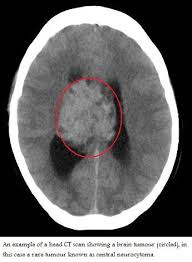

What Are The Signs Of A Brain Tumor In A Cat : Feline Meningioma Clinical Signs And Treatment Options Seattle Refined : How to detect a tumor in a cat?. Since there's limited space within the skull, signs and symptoms of a brain tumor typically develop when abnormal tissue expands and destroys or pushes on healthy brain tissue, the tissue around the. What you need to know. Persistent headaches, particularly if the person has no history of. Computed tomography (ct or cat scan). Benign brain tumors usually have clearly defined borders and usually aren't deeply rooted in brain tissue.

Brain Tumors In Cats Petmd from www.petmd.com In the sections below, we look at several types of brain tumor and their specific symptoms however, signs that a headache could be a symptom of a brain tumor include: A tumor forms when cells divide abnormally and rapidly. Brain tumours in dogs and cats are unfortunately as common as they are in people. Since there's limited space within the skull, signs and symptoms of a brain tumor typically develop when abnormal tissue expands and destroys or pushes on healthy brain tissue, the tissue around the. Symptoms may arise because of impairment tumors in the upper regions of the brain may also affect the brainstem if they cause pressure resulting in brain tissue herniating (getting pushed). This allows doctors to see inside the body without cutting it open and the procedures is commonly used to find problems inside the skull, such as brain tumors or signs of a stroke. Overall, seizures are a more common sign of a brain tumor in dogs, while behavior change is more common in cats. After taking note of clinical signs and conducting basic blood work, your vet performs an ultrasound or magnetic resonance imaging on your cat's head to diagnose a brain.